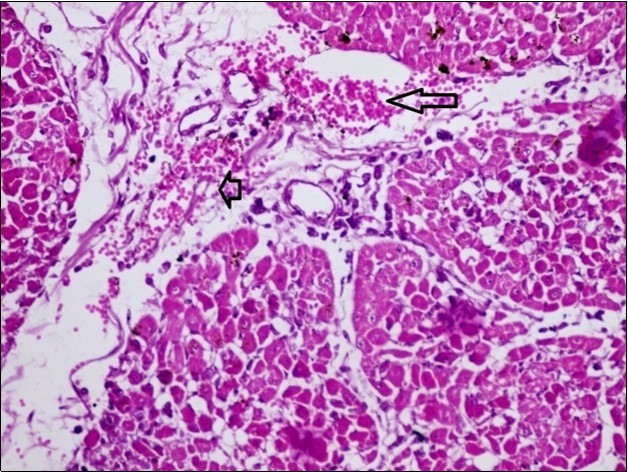

Figure 8.spleen (dead cattle less than 1 year old) showed severe depletion of lymphocytes with necrosis of endothelial lining or splenic arterioles (arrows). (Hematoxylin and fuchsin X 60)

Figure 10.Heart (dead cattle less than 1 year old) showed area of extravasated blood with few inflammatory WBCs (arrows). (Hematoxylin and fuchsin X 40)